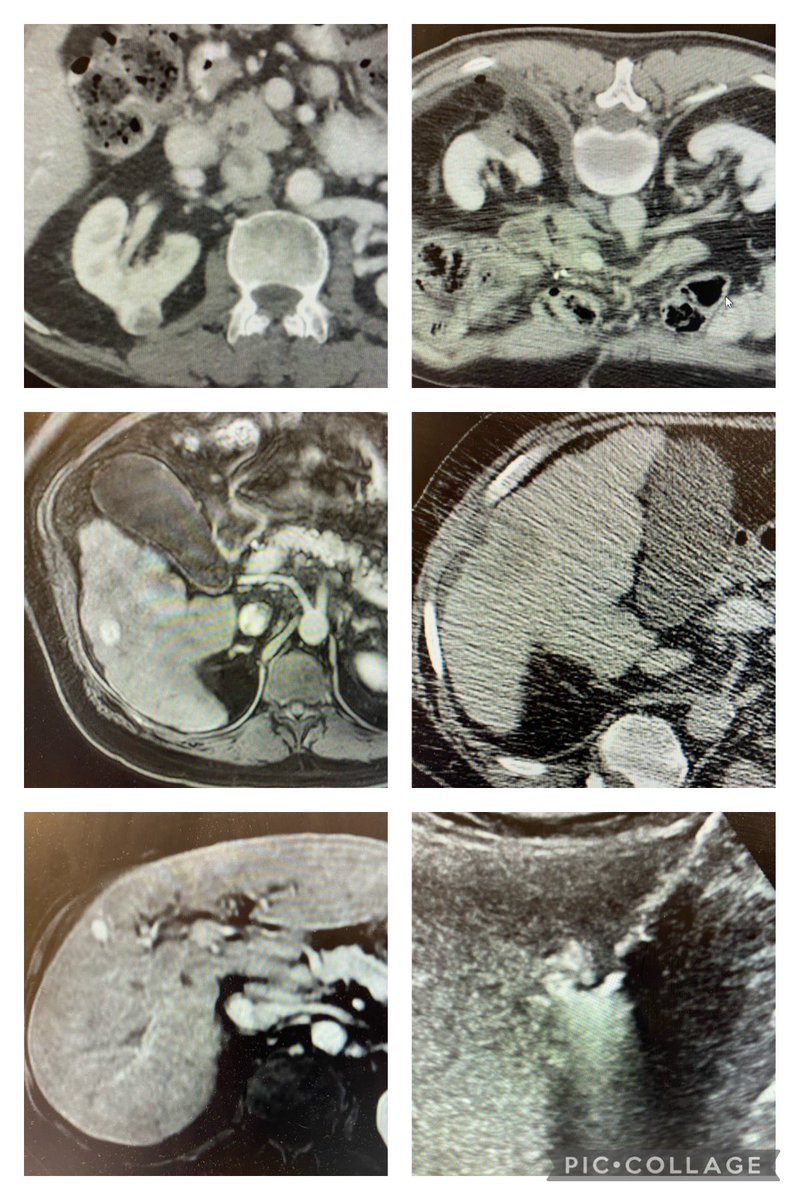

Malignant SVC syndrome w/ stridor; central upper extremity/IJ #DVT; @InariMedical FlowTriever for acute thrombus and ClotTriever for more than expected subacute/chronic; @BDandCo #Venovo for reconstruction @RonaldWinokurMD @TJUHospital @JeffersonRads @kekstero78 @carin_gonsalves